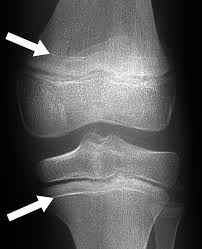

Representative Images Of Each Ossification Grade. White Arrows Indicate...  | Download Scientific Diagram

Representative Images Of Each Ossification Grade. White Arrows Indicate… | Download Scientific Diagram